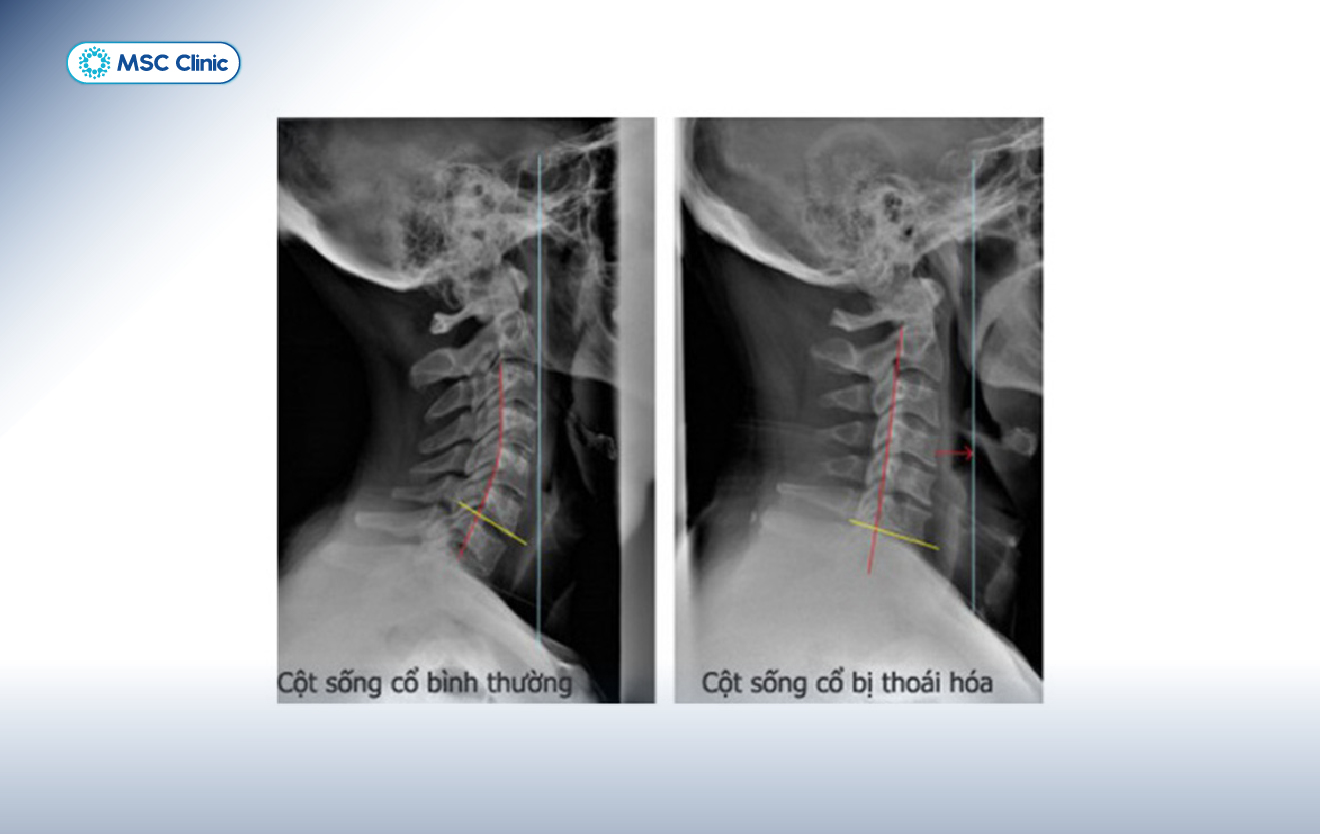

Dây chằng có nhiệm vụ giữ cho các đốt sống cổ ổn định. Khi dây chằng bị yếu hoặc tổn thương, các đốt sống có thể di chuyển không đúng vị trí. Tình trạng này có thể dẫn đến:

Dây chằng cổ bị giãn không được điều trị làm đẩy nhanh quá trình thoái hóa đốt sống cổ